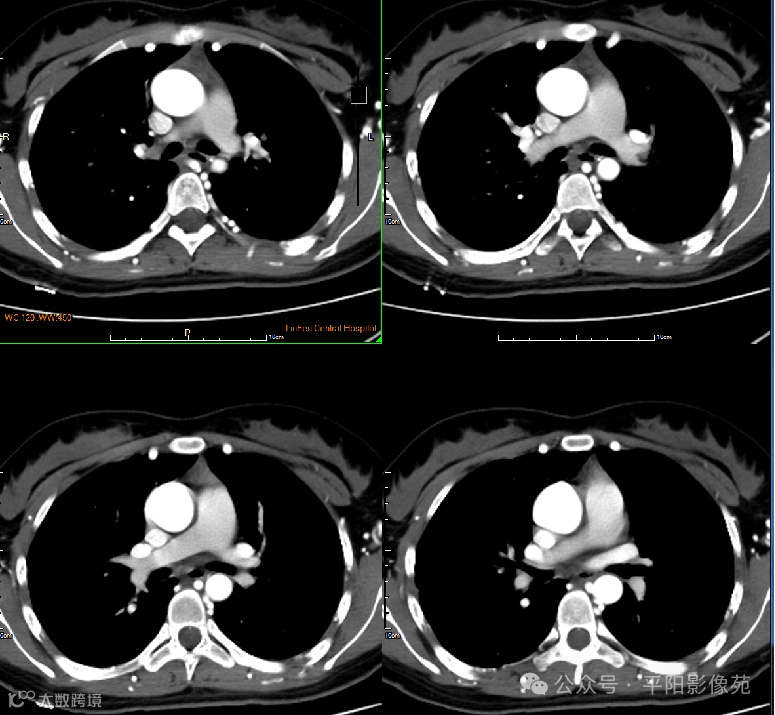

影像检查